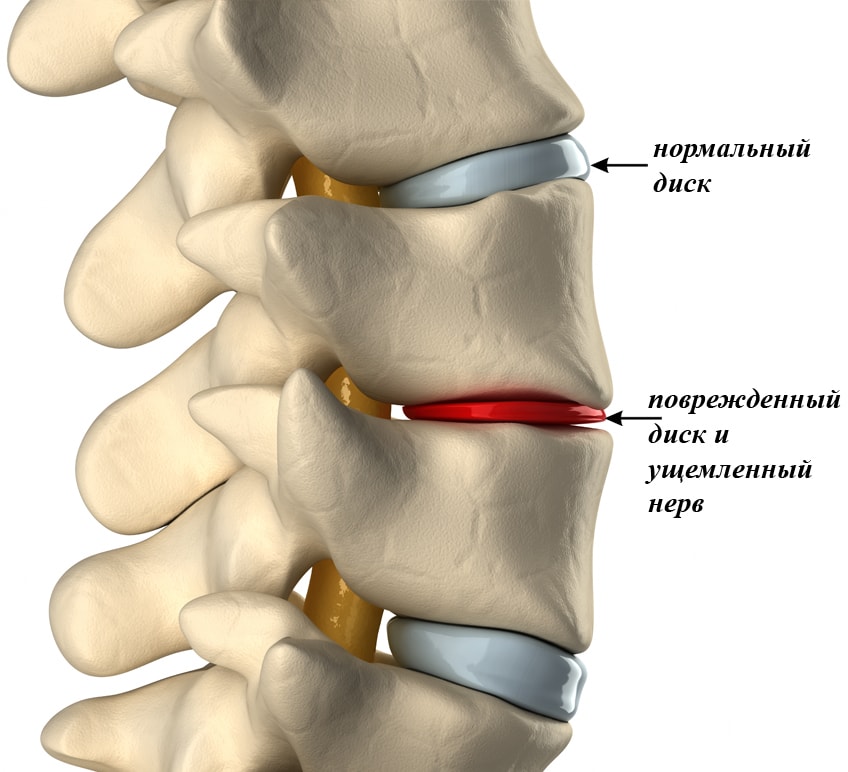

От спинного мозга нервные окончания расходятся по всему телу, проникая в каждую мышцу. В случае возникновения провоцирующих факторов может произойти защемление нерва под лопаткой рядом расположенными позвонками или новообразованием в области позвоночника.

Защемление нерва в левой или правой лопатке возникает и на фоне серьезных заболеваний. Одно из таких – остеохондроз позвоночника, который протекает с разрушением суставного хряща, что создает условия для сдавления рядом расположенных нервов. Исправить ситуацию можно, вылечив первичную патологию.

- грыжа межпозвонкового диска или выход пульпозного ядра наружу за счет разрыва фиброзного кольца;

При сдавливании нервных окончаний соседними позвонками, протрузией, грыжей или спазмированными мышечными тканями возникает защемление нерва. Такая патология характеризуется значительными болями, которые заставляют пациента предпринимать какие-либо меры, чтобы облегчить свое состояние. Чем грозит защемление нерва в спине и под лопаткой и как лечить расскажет данная статья.